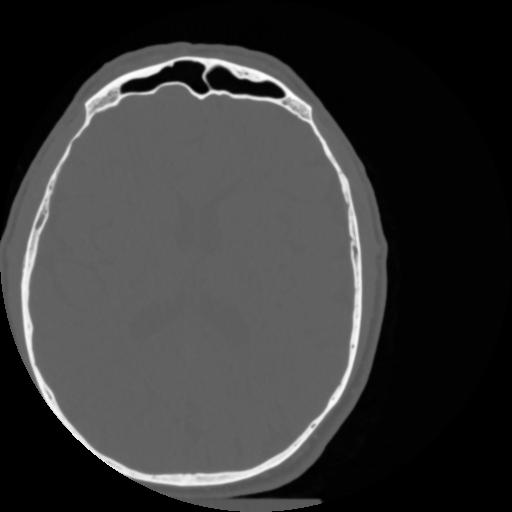

4 CEREBRO,,Vol,0.5,CEREBRO,,